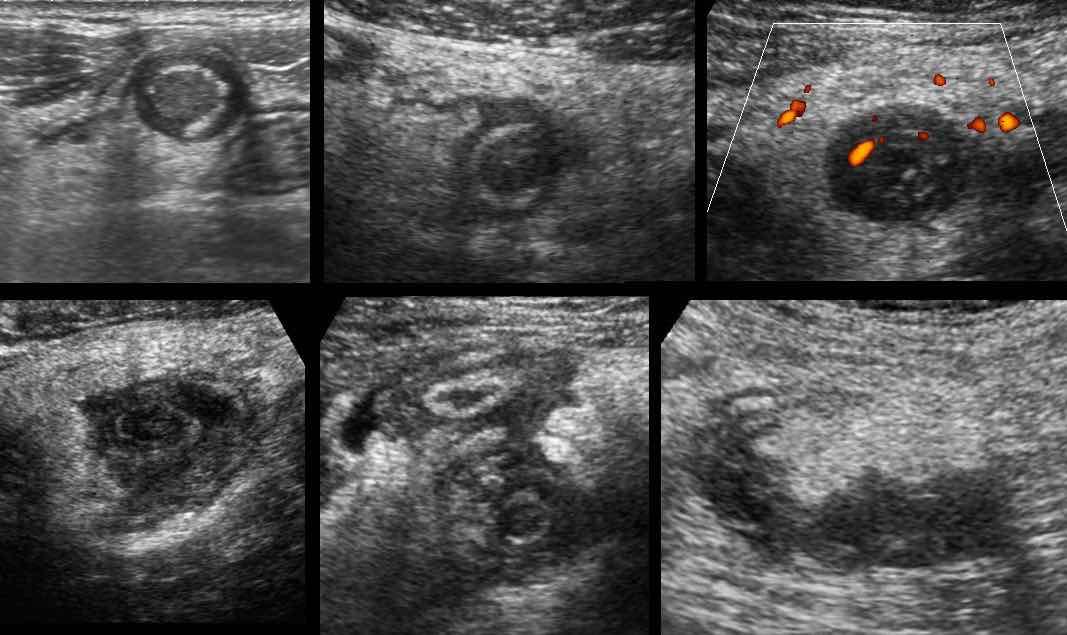

Ở bệnh nhân rất gầy này với viêm ruột thừa cấp giai đoạn sớm, siêu âm cho thấy hình ảnh giãn đoạn xa của ruột thừa.

Trên mặt phẳng A, siêu âm Doppler cho thấy tình trạng tăng sinh mạch máu mạnh ở thành ruột thừa; tuy nhiên trên mặt phẳng B, không quan sát thấy mạch máu trong thành ruột thừa do áp lực trong lòng cao.

Lưu ý hình ảnh ruột thừa giãn, tròn, không thể ép xẹp trong mặt phẳng B, phồng vào thành bụng khi ấn (đầu mũi tên), với tín hiệu mạch máu chỉ còn ở vùng mạc treo ruột thừa có mỡ xung quanh.